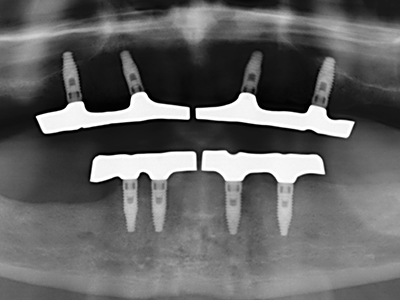

Indication: Preparation near nerves

As noted above, indications for piezosurgery can also be found in the field of conservative dental surgery. Special working tips simplify the exposure of root tips and make it easier to protect nerves and sinus mucous membranes, particularly in the lower premolar and upper posterior tooth regions. Angled diamond tips are used to precisely prepare the resection cavity for the retrograde root filler material for unsealed apical obturation. The ultrasonic technology means the tips can be very slender, which improves the view and the size of the access cavity. As a result, the application of ultrasonic surgery for this indication is one of the standard procedures for apical resection (Del Fabbro, Tsesis et al. 2010, Scarano, Artese et al. 2012).

Indication: Apical resection

When surgical procedures are performed on bone in the immediate vicinity of sensitive structures such as blood vessels or nerves, rotary instruments pose a significant risk of iatrogenic injury. Piezoelectric devices can be helpful for preparation of bone covers and removal of hard tissue close to nerves, particularly for exposure of nerves after iatrogenic injury but also during nerve lateralization for resective and reconstructive procedures or implant placement (Fig. 17-20). Light contact between the piezotip and the nerve does not generally result in damage but proceeding incautiously with saw-like motions or attachments where a residual bone substrate remains may cause temporary or even permanent nerve damage. However, the risk of damage is considered to be substantially lower than when using saws or milling instruments (Pereira, Gealh et al. 2014).